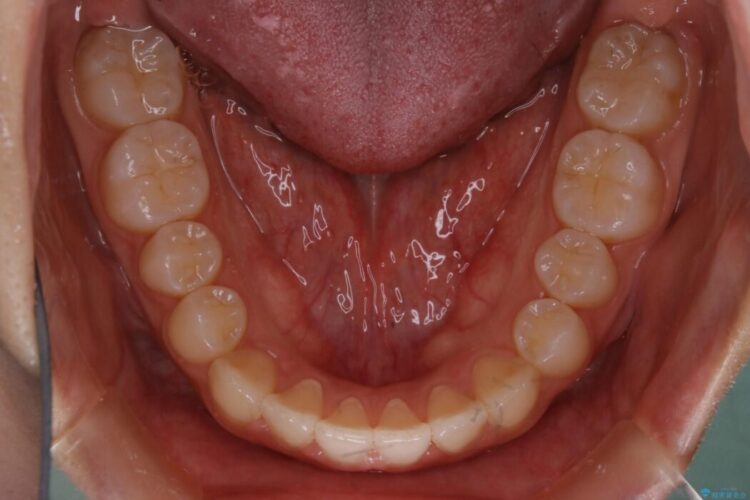

治療後について

正常な噛み合わせ位置へと改善したことにより奥歯で噛みしめることができ、加えて見た目も受け口から変わって大変ご満足いただけました。